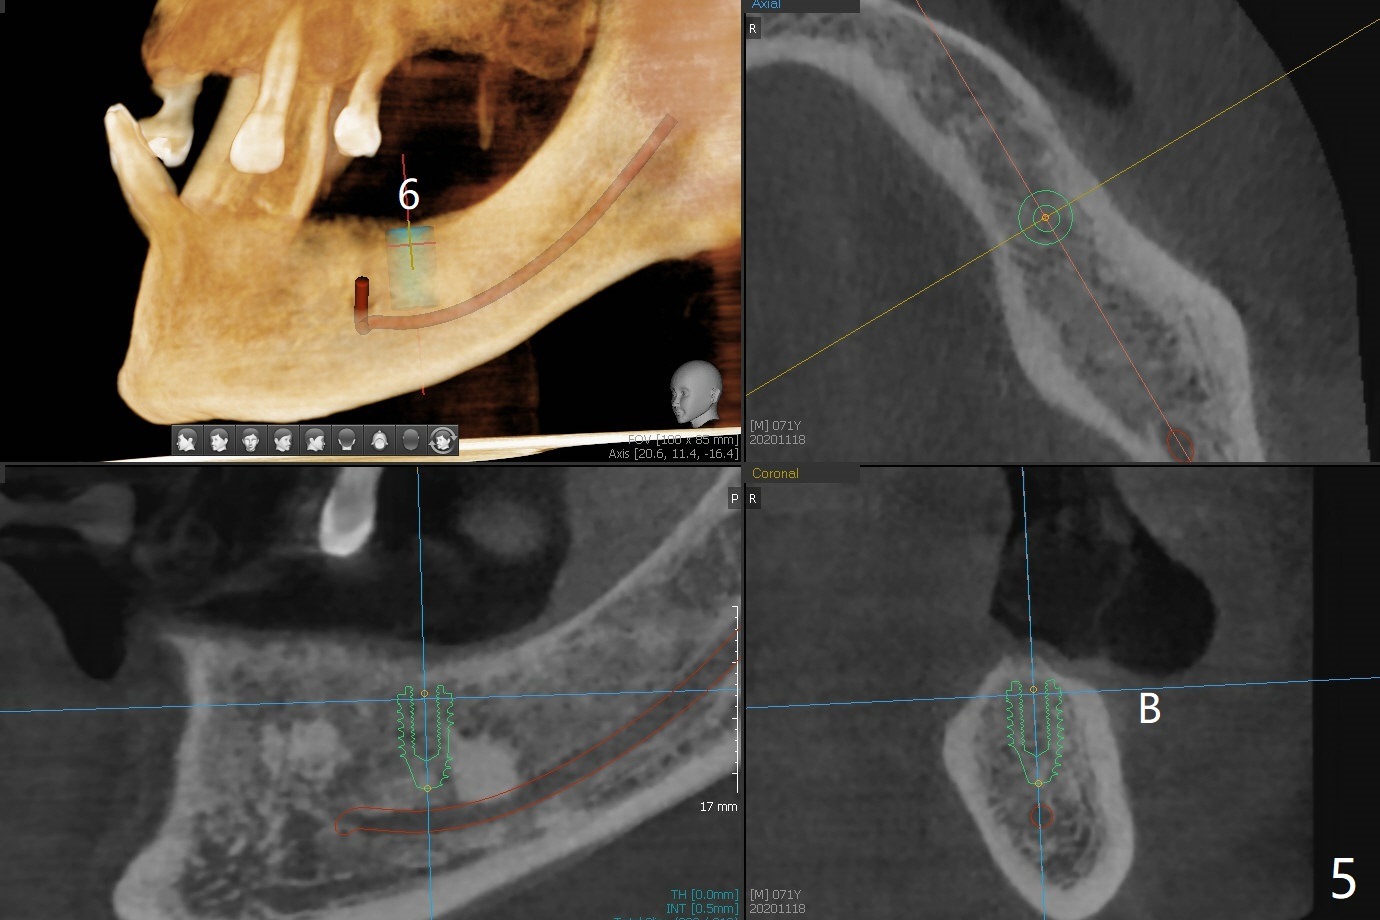

71岁男主诉下颌局部托牙松动(图一),侧切牙不适,临床检查显示后者有咬合创伤,局部卫生不佳,对策:洗牙以及左下4,6植入植体,放置带有球的基台(图五,六)。上颌局部托牙有三个自然牙,挺稳定,但是颈部缺损严重,需要修补(图二,三),左上5远中龋齿需要根管治疗(图四),尽量延长基牙寿命。一个月后病人回来却要求处理松动疼痛右下2,不愿意种植,与3固定和调整咬合,症状消失。Return to No Caries Overdentures Xin Wei, DDS, PhD, MS 1st edition 11/18/2020, last revision 12/13/2020